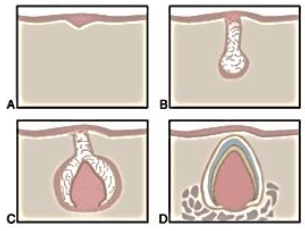

As imagens a seguir mostram as etapas de formação de um dente decíduo. Analise-as.

Qual é o estágio de formação indicado pela letra C?